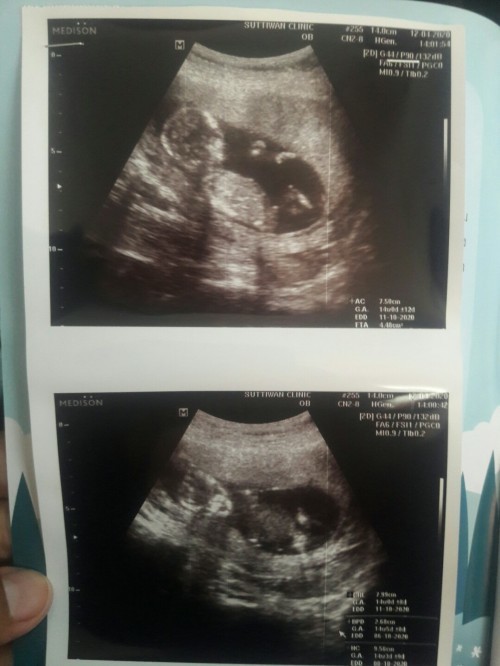

แม่ๆคนไหนมีภาพอัลตร้าซาวด์ประมาณ13วีคบ้างคะ ของเรา13วีค ภาพแบบนี้ค่ะ ดูไม่ออกเลย?

13week. จ้า❤

13วีคจ้า

13weeksคร้า

13 week ค่ะ

13วิคคะ